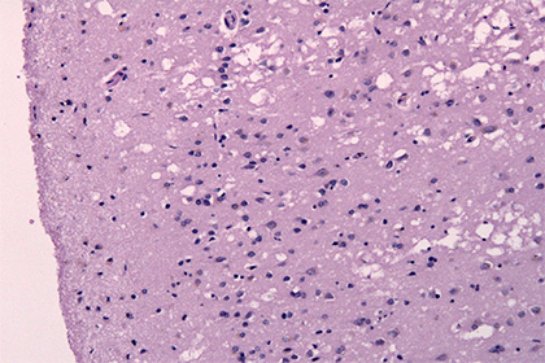

Джон Коллиндж (John Collinge) и его коллеги провели вскрытие и анализ тканей

Риск заражения неизлечимыми нейродегенеративными болезнями через инъекции гормонов роста, полученных от трупов, можно считать доказанным. Ученые призывают тщательно исследовать и другие ятрогенные пути переноса прионов (через хирургические инструменты и переливание крови), чтобы понять, не несут ли и они риск заражения болезнью Альцгеймера.